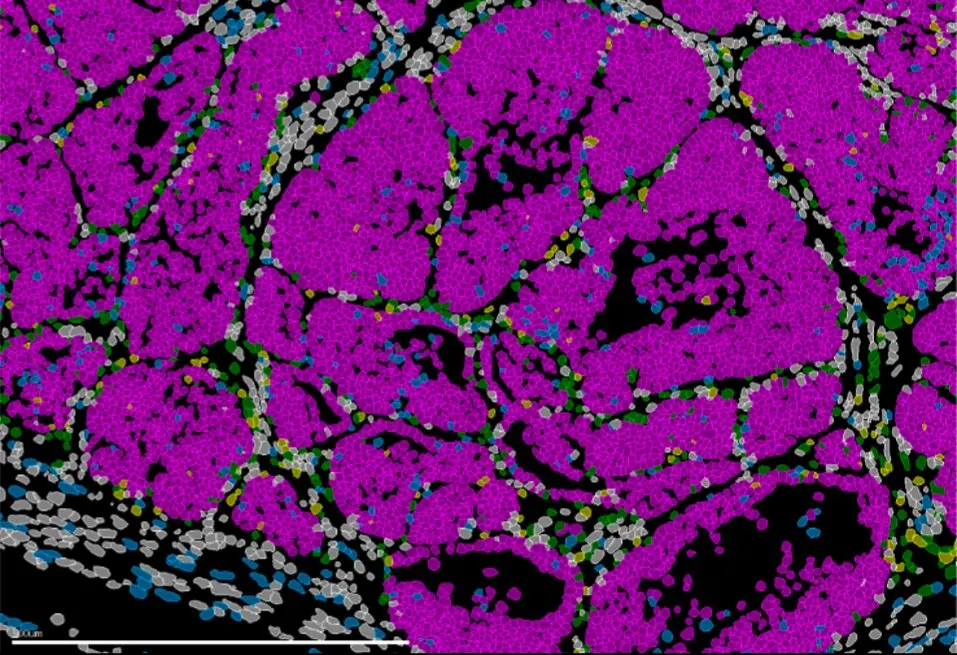

Tumor de mama en ratón con células cancerosas (rosa). IN CSIC-UMH

photo_camera Tumor de mama en ratón con células cancerosas (rosa). IN CSIC-UMH